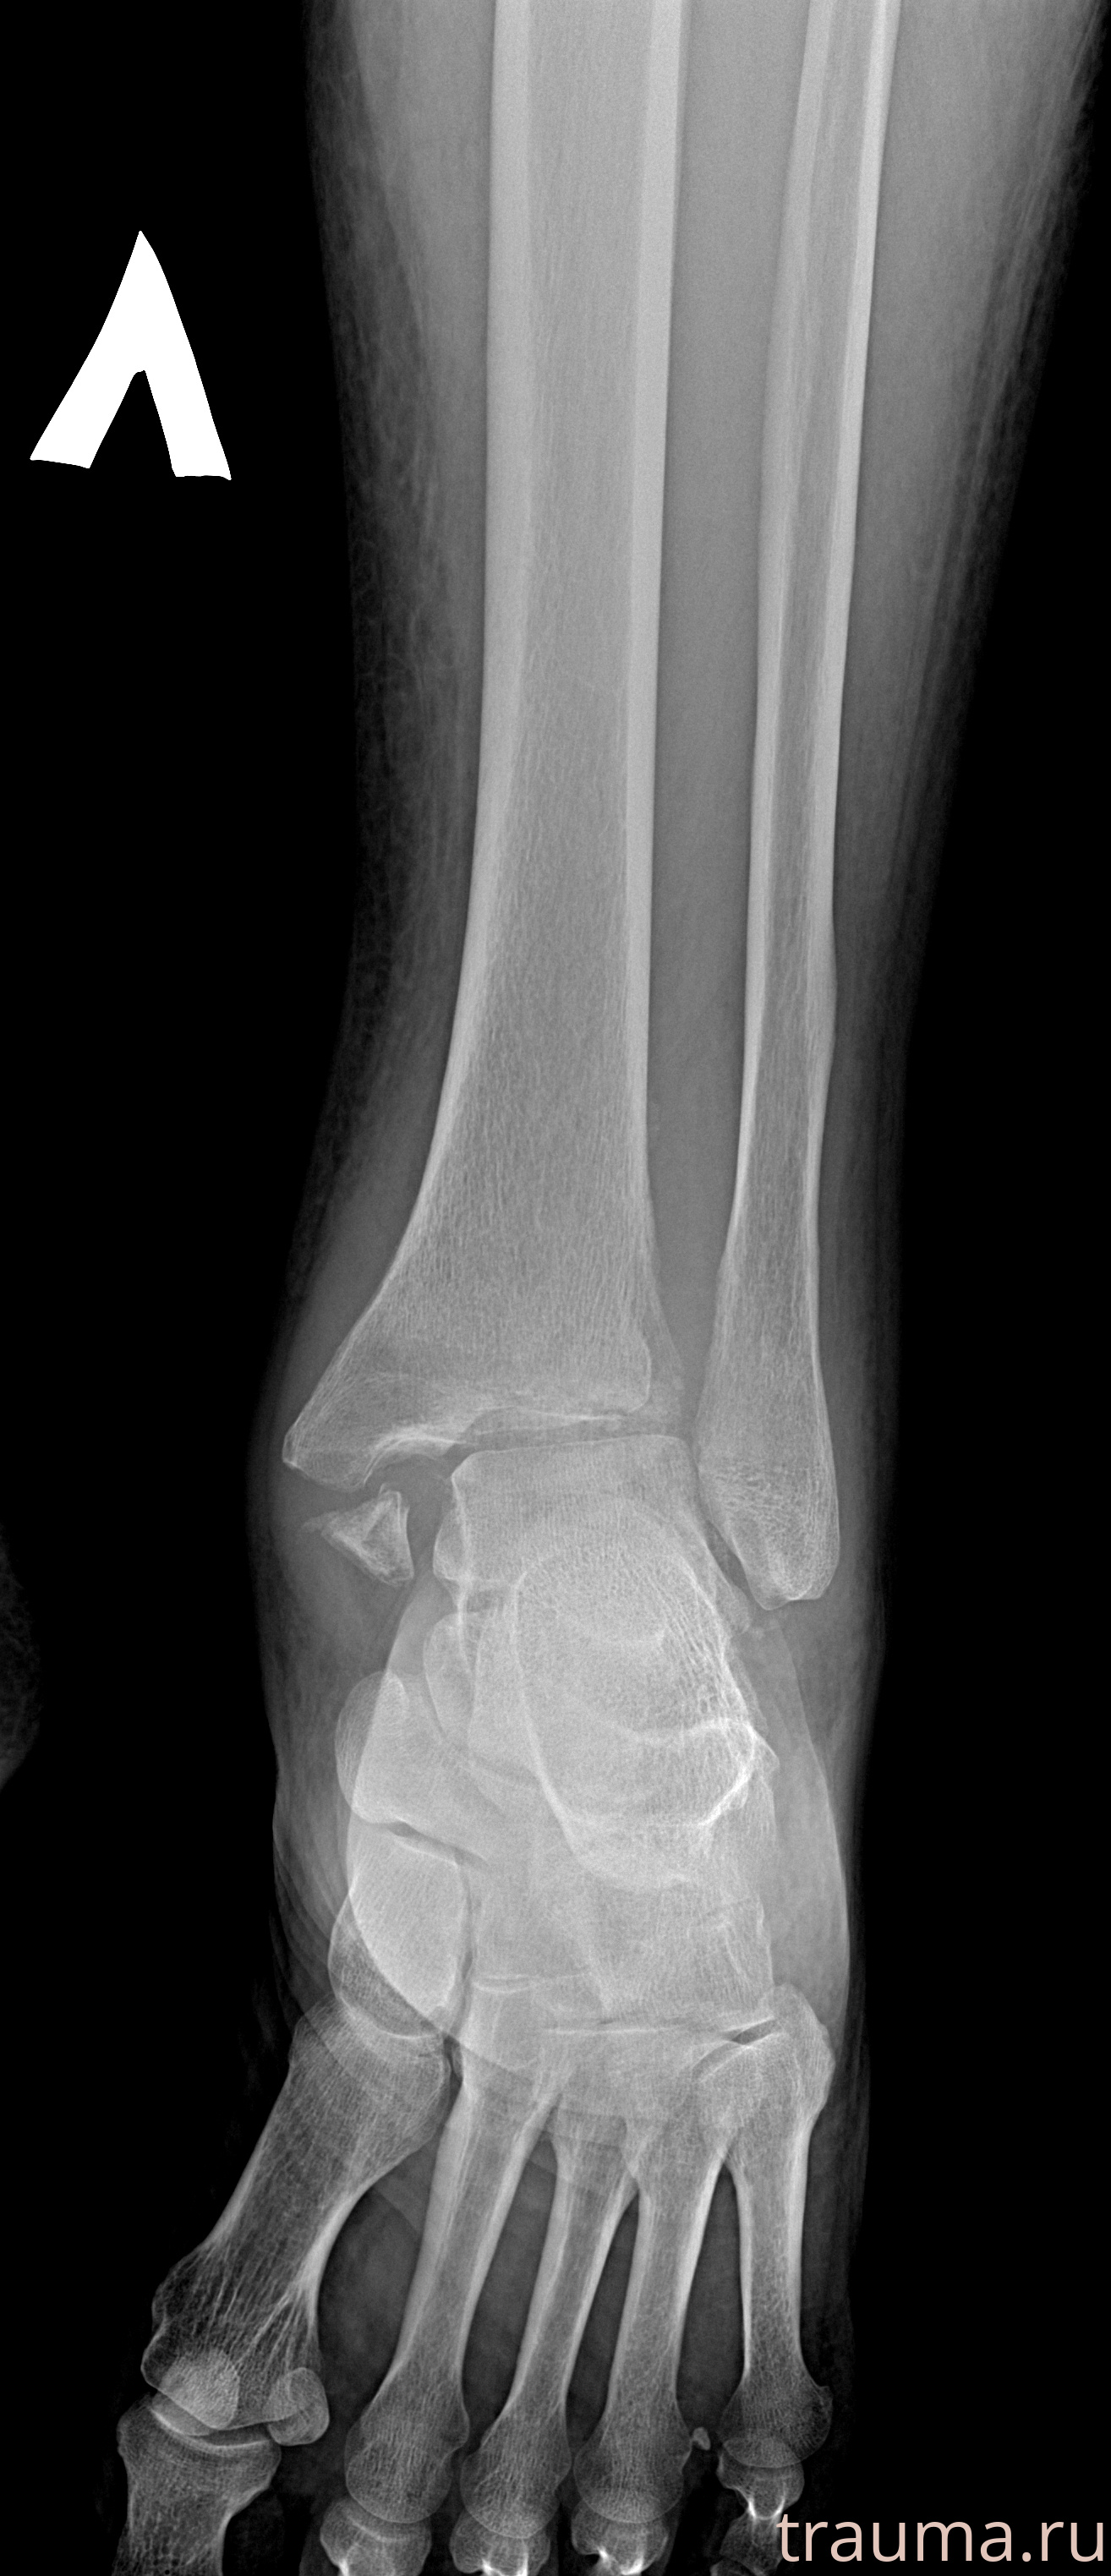

Рентгенограммы